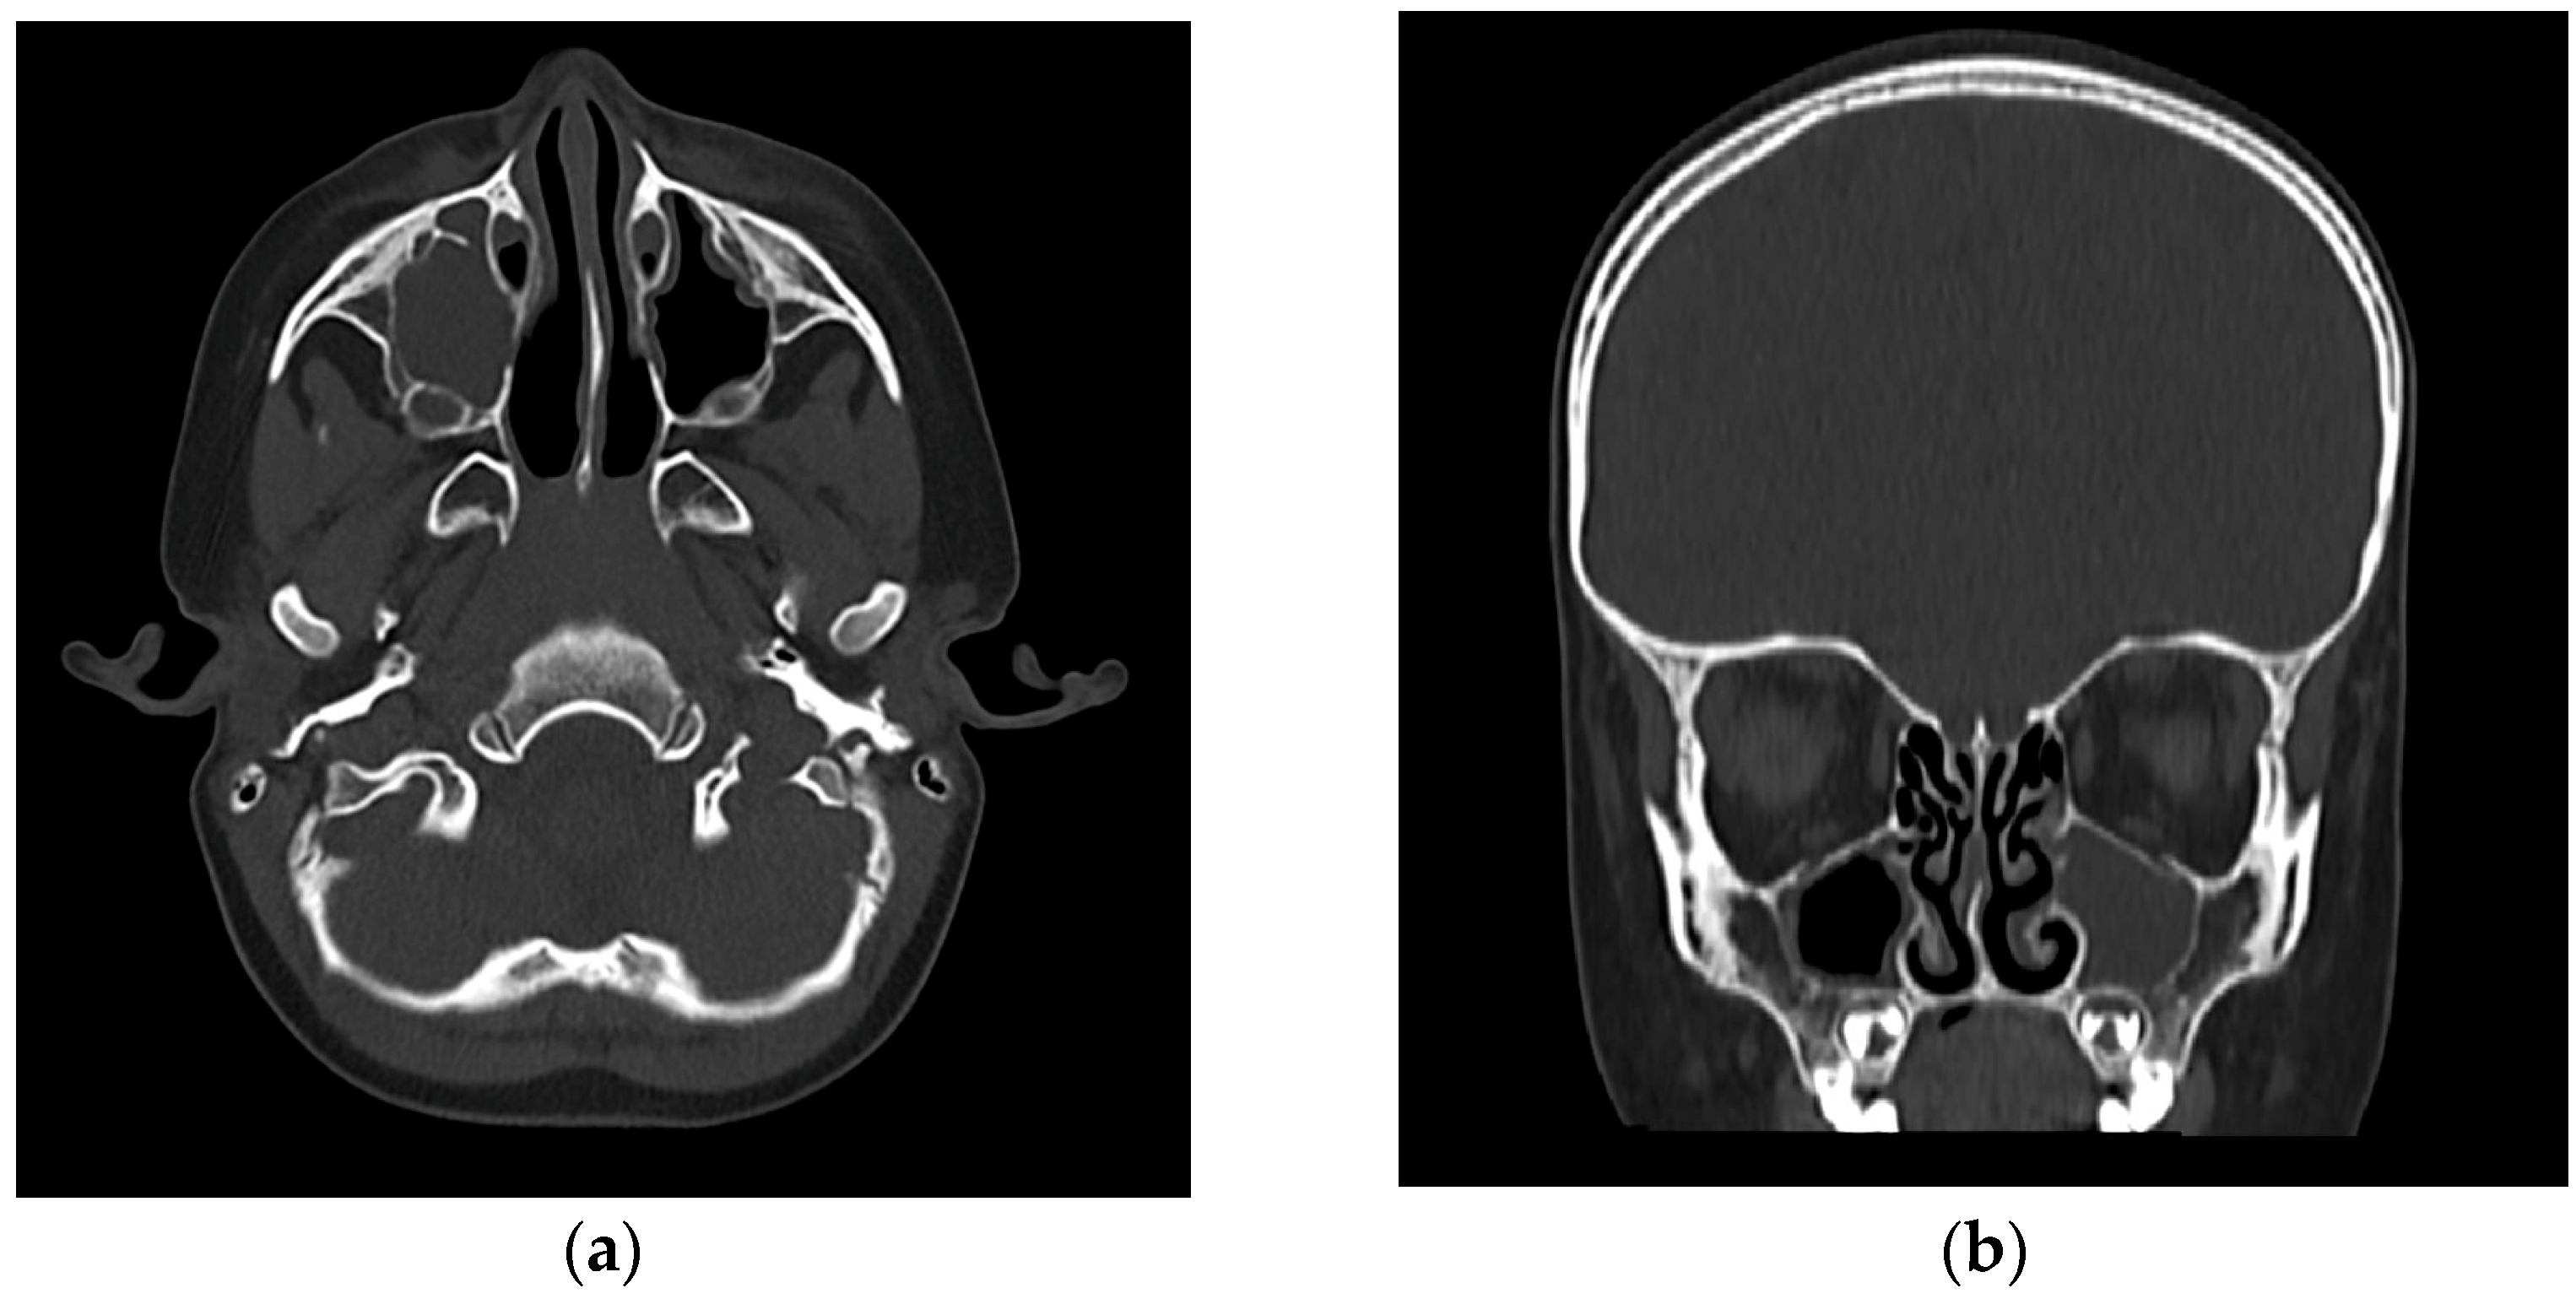

Unilateral Palpebral Edema as a Central Sign of Acute Enterobacter-Associated Rhinosinusitis in a 5-Year-Old: A Rare Pediatric Case

2. Case Presentation